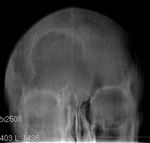

Пол пациента: Женский пол Тип патологии: Другое Область исследования: Челюстно-лицевая область и шея Методы исследования: Rg Пациентка направлена на рентгенографию лицевого черепа окулистом... https://radiomed.ru/sites/default/files/styles/case_slider_image/public/user/12/2yu201409100010.jpg?itok=K5TSWXIC ID:41802 Fri, 12/09/2014 - 13:24 #1 nbb Offline Last seen: 4 months 2 weeks ago Joined: 02.06.2012 - 22:18 Posts: 476 мукоцеле? Fri, 12/09/2014 - 13:43 #2 Катенёв Валенти... Offline Last seen: 7 years 5 months ago Joined: 22.03.2008 - 22:15 Posts: 54876 Откуда? Fri, 12/09/2014 - 13:57 #3 И.Бондаренко Offline Last seen: 1 week 5 days ago Joined: 13.09.2011 - 22:55 Posts: 9213 Интересная картинка. Пазуха или опухоль? Fri, 12/09/2014 - 14:18 #4 Daniel' Offline Last seen: 6 months 1 week ago Joined: 27.06.2013 - 22:21 Posts: 2210 nbb wrote: мукоцеле? будь МУКОцеле - было бы затенение соответствующей пазухи, и в боковой проекции выбухание кнаружи. Думаю, вариант развития нормы. Fri, 12/09/2014 - 14:58 #5 nbb Offline Last seen: 4 months 2 weeks ago Joined: 02.06.2012 - 22:18 Posts: 476 Daniel' wrote: nbb wrote: мукоцеле? будь МУКОцеле - было бы затенение соответствующей пазухи, и в боковой проекции выбухание кнаружи. Думаю, вариант развития нормы. а если санирована? Fri, 12/09/2014 - 15:31 #6 stovbav Offline Last seen: 2 years 7 months ago Joined: 20.12.2009 - 17:28 Posts: 7066 так....в виде рассуждения....подумалось о гигантоклеточной опухоли...... Болезни ног: виды, симптомы, причины, профилактика и лечение Fri, 12/09/2014 - 15:33 #7 Сольвейг Offline Last seen: 3 years 10 months ago Joined: 05.02.2013 - 20:25 Posts: 2239 На вариант развития развития пазухи больше похоже. Fri, 12/09/2014 - 19:46 #8 Андрей Юрьевич Offline Last seen: 1 week 17 hours ago Joined: 16.11.2008 - 22:16 Posts: 18106 Затемнено-не затемнено, санирована - не санирована, без подбородочно носовой проекции не скажешь. По прямому, похоже, что левая в/ч пазуха затемнена. Андрей Юрьевич Mon, 15/09/2014 - 09:41 #9 Катенёв Валенти... Offline Last seen: 7 years 5 months ago Joined: 22.03.2008 - 22:15 Posts: 54876 Фрагменты рентгенограмм.Приложения: Mon, 15/09/2014 - 09:42 #10 Катенёв Валенти... Offline Last seen: 7 years 5 months ago Joined: 22.03.2008 - 22:15 Posts: 54876 stovbav wrote: так....в виде рассуждения....подумалось о гигантоклеточной опухоли...... Была такая "мысля"... Mon, 15/09/2014 - 09:43 #11 Катенёв Валенти... Offline Last seen: 7 years 5 months ago Joined: 22.03.2008 - 22:15 Posts: 54876 Андрей Юрьевич wrote: Затемнено-не затемнено, санирована - не санирована, без подбородочно носовой проекции не скажешь. По прямому, похоже, что левая в/ч пазуха затемнена. А "та" проекция сомнения развеет? Mon, 15/09/2014 - 16:21 #12 nbb Offline Last seen: 4 months 2 weeks ago Joined: 02.06.2012 - 22:18 Posts: 476 Признаки прерывания кортикального слоя?Приложения: Mon, 15/09/2014 - 17:12 #13 Евгений Второй Offline Last seen: 4 months 2 weeks ago Joined: 13.09.2011 - 22:00 Posts: 1772 Могу предположить арахноидальную киту. Tue, 16/09/2014 - 09:39 #14 Катенёв Валенти... Offline Last seen: 7 years 5 months ago Joined: 22.03.2008 - 22:15 Posts: 54876 Томограммы.Приложения: Wed, 17/09/2014 - 09:08 #15 Катенёв Валенти... Offline Last seen: 7 years 5 months ago Joined: 22.03.2008 - 22:15 Posts: 54876 Томограммы в прямой проекции, правда "хреновые" - три среза.Приложения: Wed, 17/09/2014 - 10:23 #16 stovbav Offline Last seen: 2 years 7 months ago Joined: 20.12.2009 - 17:28 Posts: 7066 и каков же результат?...только то, что ЭТО не пазуха?..... Болезни ног: виды, симптомы, причины, профилактика и лечение

Интересная картинка. Пазуха или опухоль?

Затемнено-не затемнено, санирована - не санирована, без подбородочно носовой проекции не скажешь. По прямому, похоже, что левая в/ч пазуха затемнена.

Фрагменты рентгенограмм.